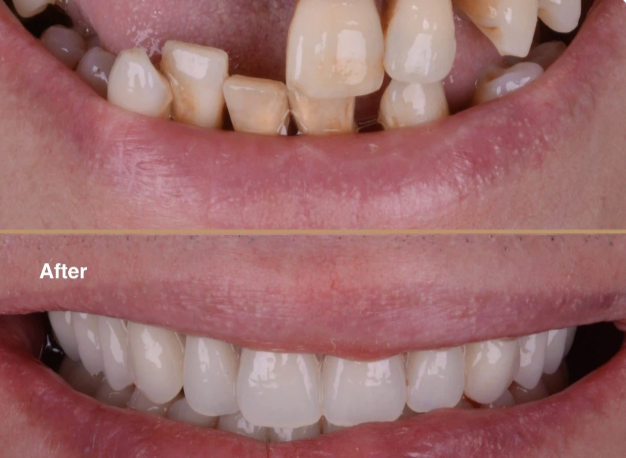

Smile Lifts with Cosmetic Veneers - eneers are thin shells made of porcelain or composite resin which sit like a laminate on the front surface of your tooth. It serves to cover up cracked, chipped or unsightly teeth see our gallery.

Smile Lifts with Cosmetic Veneers

Veneers are thin shells covering cracked, chipped teeth. They can be applied to one or more teeth. Made of porcelain or resin, with resin being more cost-effective and easier to repair.